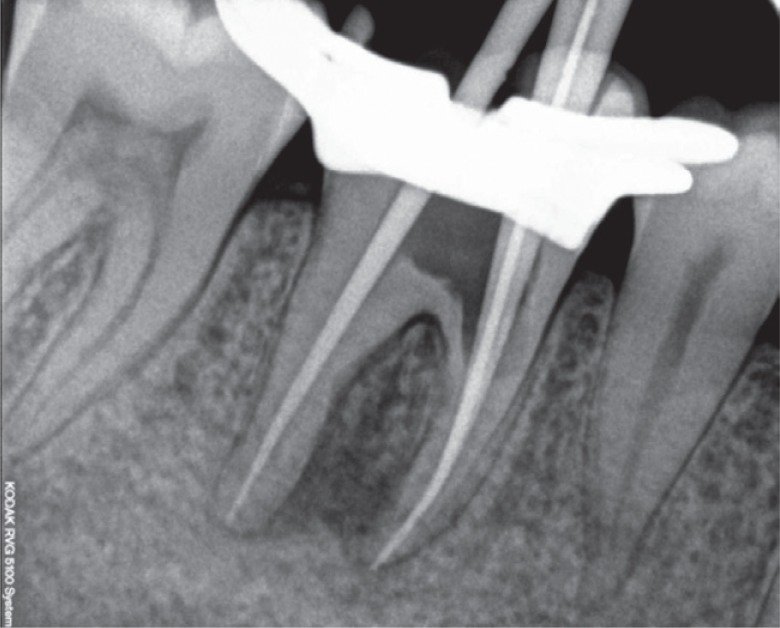

Figure 3Working length determination radiograph.